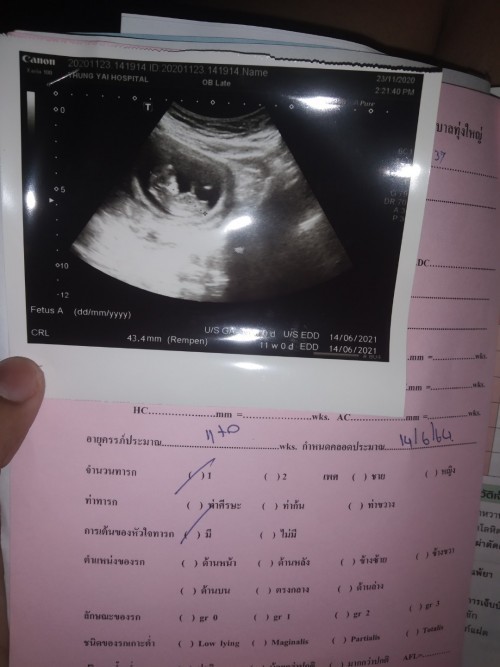

ขอสอบถาม 13สัปดาห์แล้วน้องยังไม่เป็นตัว คนอื่นเป็นเหมือนกันไหมคะ แต่หมอบอกหัวใจน้องเต้น กังวลคะ จะเป็นไรไหม

ซาวตอน13wค่ะก็เห็นแล้วนะคะ

บ้านนี้ 13wคะ เป็นตัวแล้ว